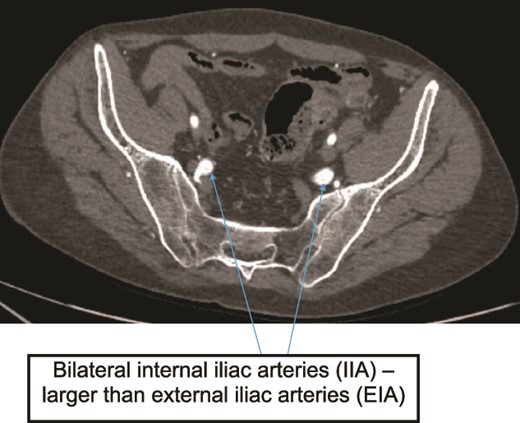

Case 2—axial image of LL CTA of pelvic cavity showing the IIAs larger size compared to the external iliac arteries.